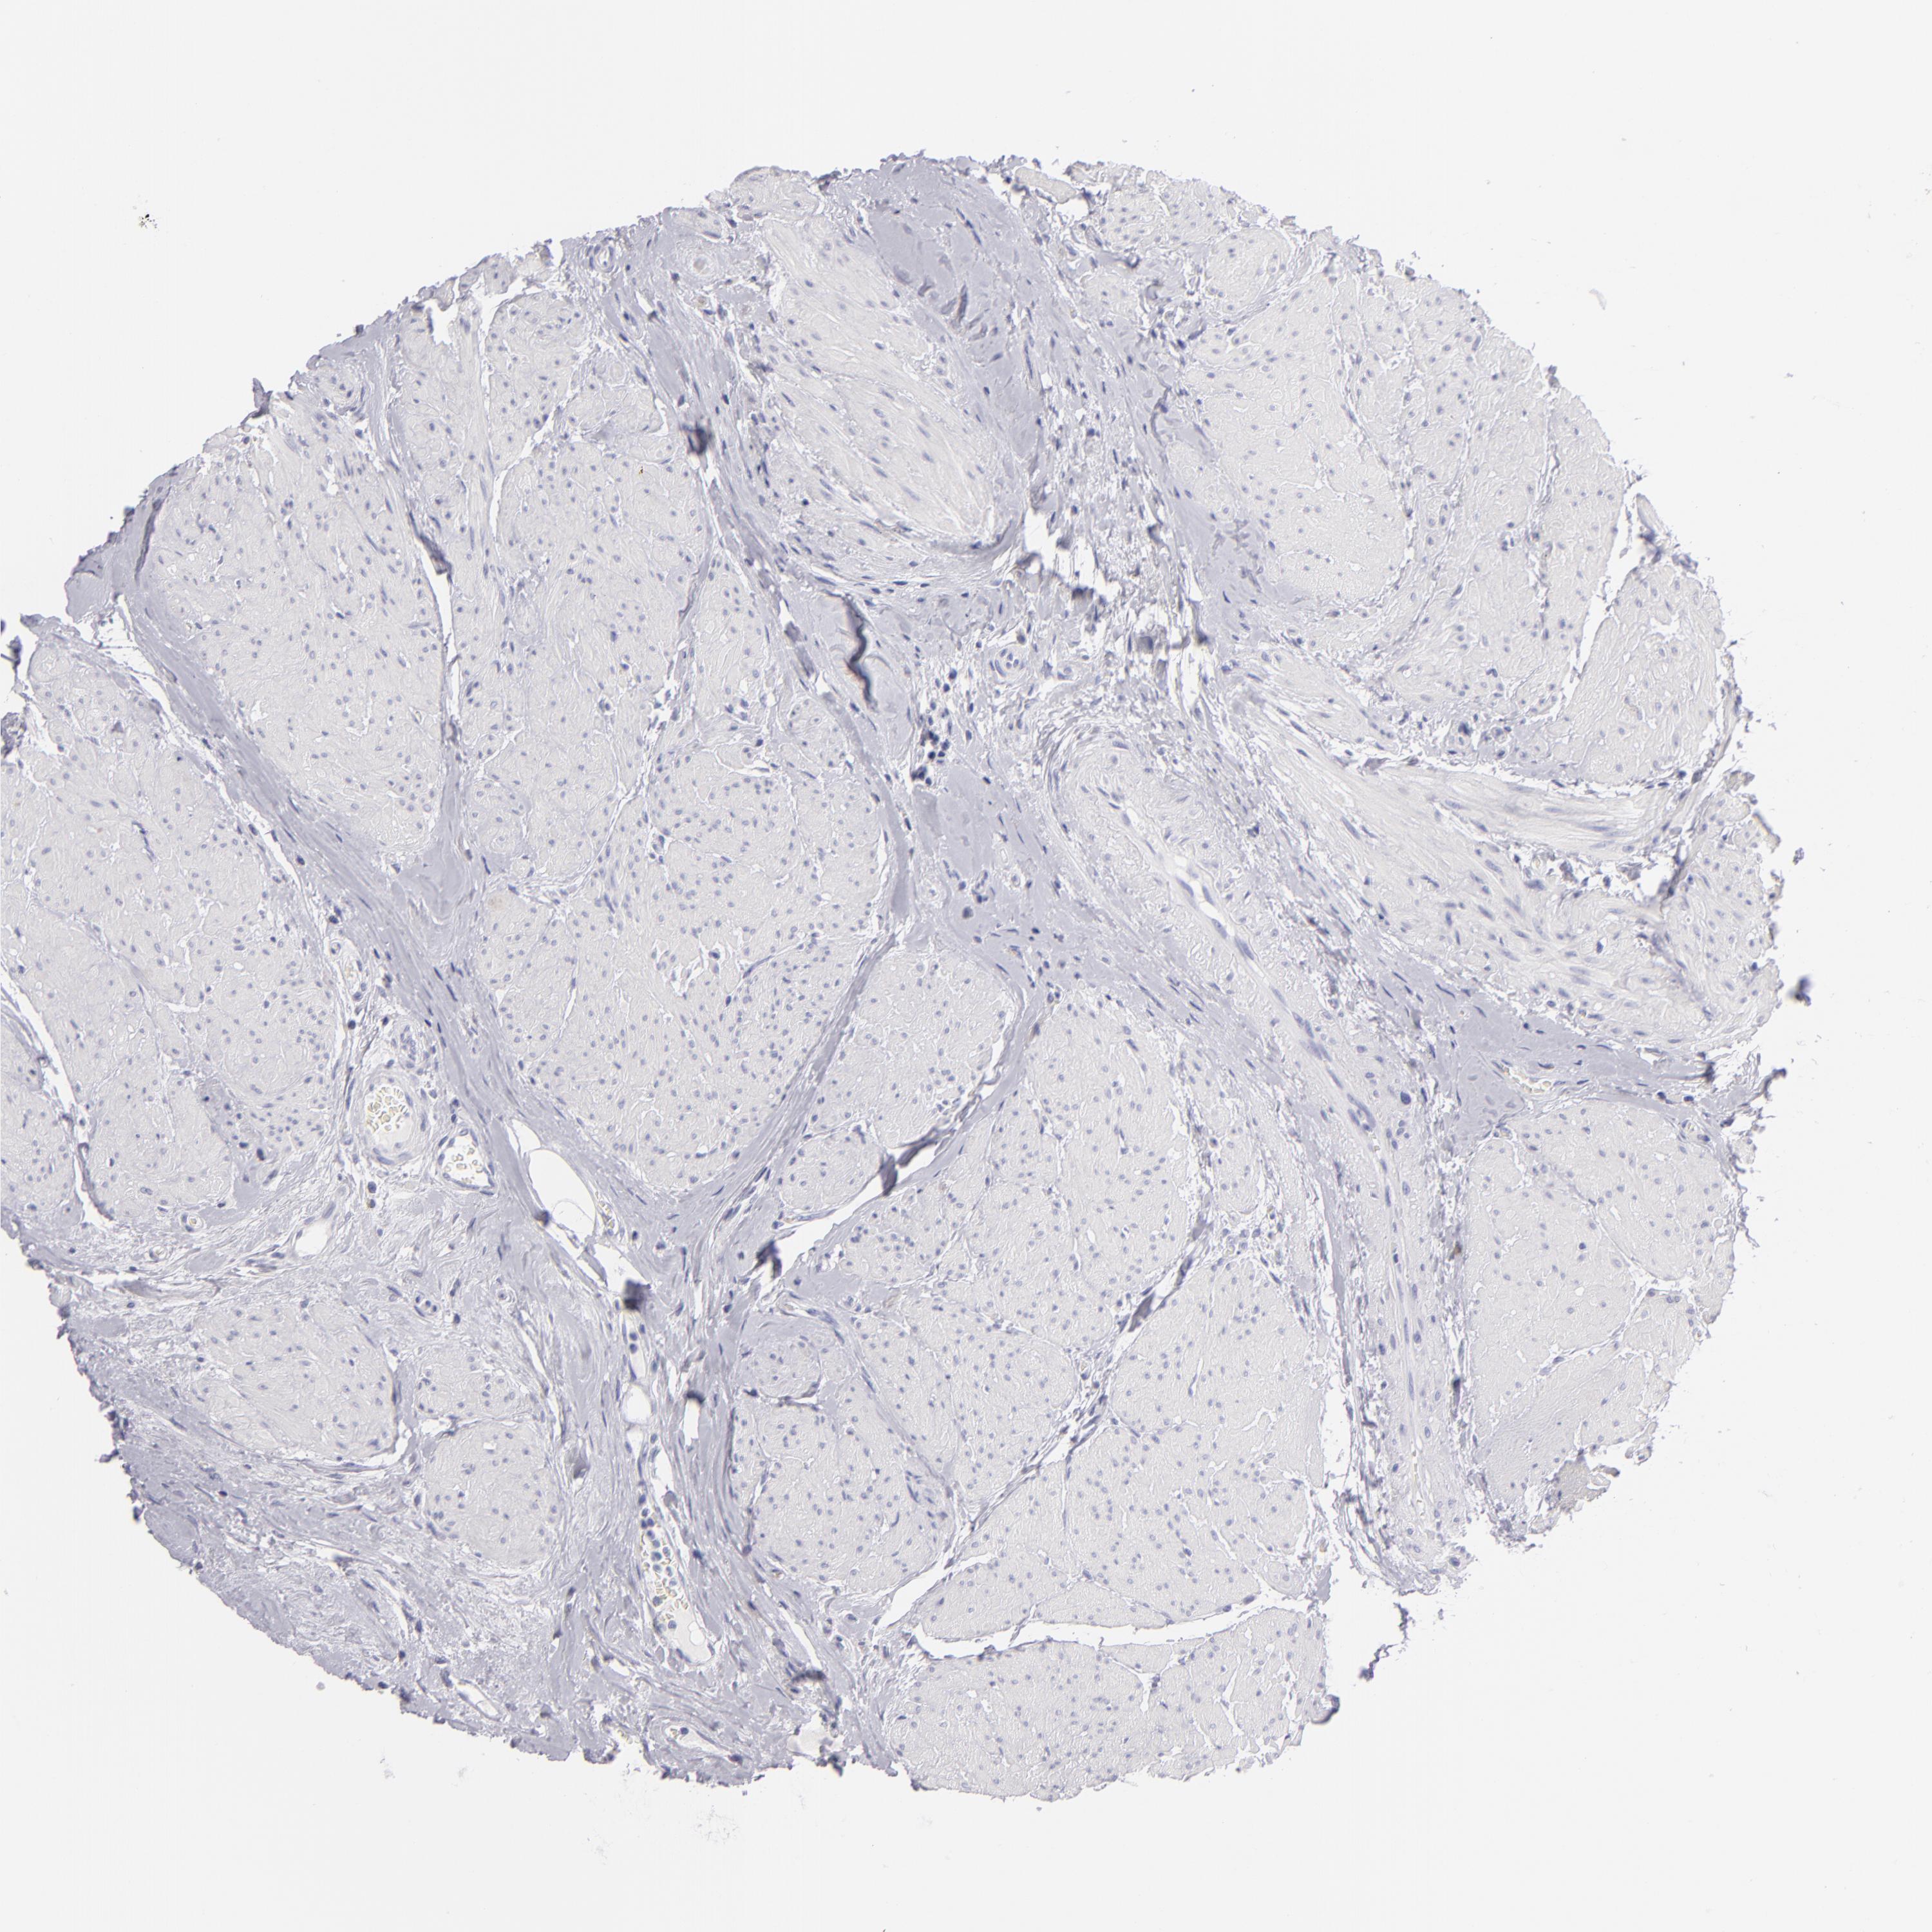

UROTHELIAL CANCER - Protein expressioni

A mouse-over function shows sample information and annotation data. Click on an image to view it in a full screen mode. Samples can be filtered based on level of antibody staining by selecting one or several of the following categories: high, medium, low and not detected. The assay and annotation is described here.

Note that samples used for immunohistochemistry by the Human Protein Atlas do not correspond to samples in the TCGA dataset.

Antibody stainingi

Antibody staining in the annotated cell types in the current human tissue is reported as not detected, low, medium, or high, based on conventional immunohistochemistry profiling in selected tissues. This score is based on the combination of the staining intensity and fraction of stained cells.

Each image is clickable and will lead to virtual microscopy that enables deeper exploration of all samples and also displays staining intensity scores, fraction scores and subcellular localization as well as patient and tissue information for each sample.

Antibody HPA006884

Antibody HPA006885

Antibody CAB002452

Urothelial carcinoma, Low grade

Urothelial carcinoma, High grade

Adenocarcinoma, NOS